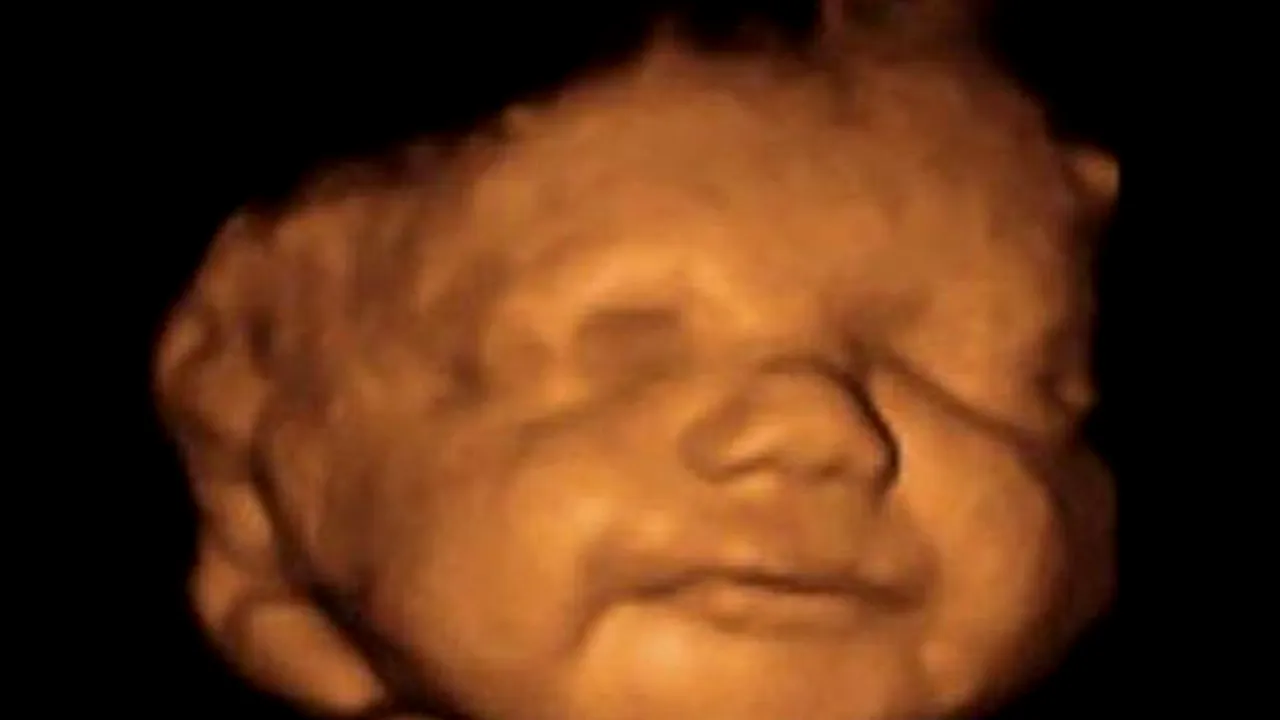

Femeia a dezvăluit că nu s-a putut gândi la un avort, mai ales după ce a primit una din ecografii și i-a văzut fața micuțului nenăscut. Aceasta a precizat că în momentul în care a văzut imaginea a simțit că cel mic își dorește să trăiască.